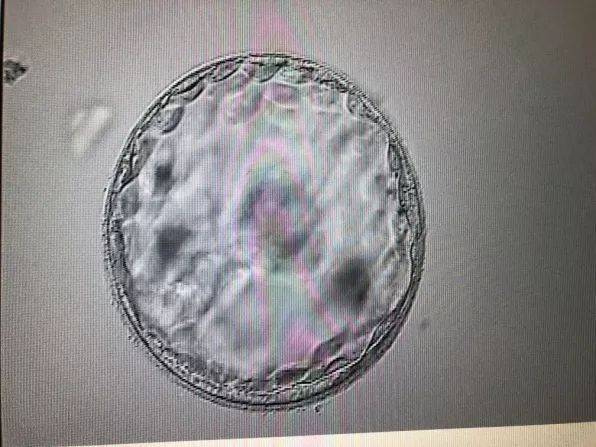

早孕试纸是一种通过检测尿液中的人绒毛膜促性腺激素(hCG)水平来判断是否怀孕的快速检测工具。hCG是一种由胚胎滋养层细胞分泌的激素,在怀孕初期,hCG水平会迅速升高。

早孕试纸的检测原理是:当尿液中hCG含量达到一定水平时,试纸上的检测线会变深,表明怀孕的可能性较大。如果检测线颜色较浅,可能表示hCG水平较低,怀孕的可能性较小。